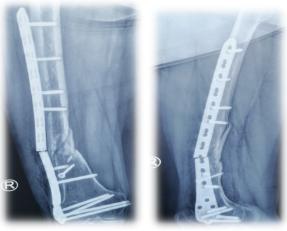

骨不连门诊术后复查X线片及功能

患者住院后,在西安市红会医院副院长、骨创伤医院院长张堃及李忠主任团队的研讨下,为杨女士制定了最为合理的个性化方案——“通道成骨”技术。之后,手术顺利完成,在医生的专业指导下逐步恢复功能锻炼。术后4个月,杨女士完全康复,并对医院的医护人员表示感谢。